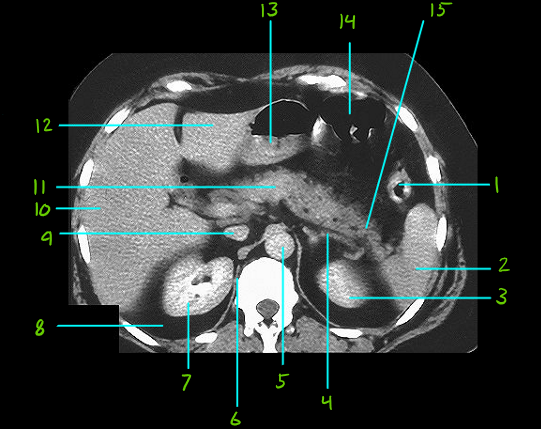

1

What is #1

Descending colon

What is #2

Spleen

What is #3

Left kidney

What is #4

Left adrenal gland

What is #5

Aorta

What is #6

Diaphragm

What is #7

Right kidney

What is #8

Parirenal fat

What is #9

Inf. Vena cava

What is #10

Right lobe of liver

What is #11

Pancreas body

What is #12

Left lobe of liver

What is #13

Pyloric antrum

What is #14

Transverse colon